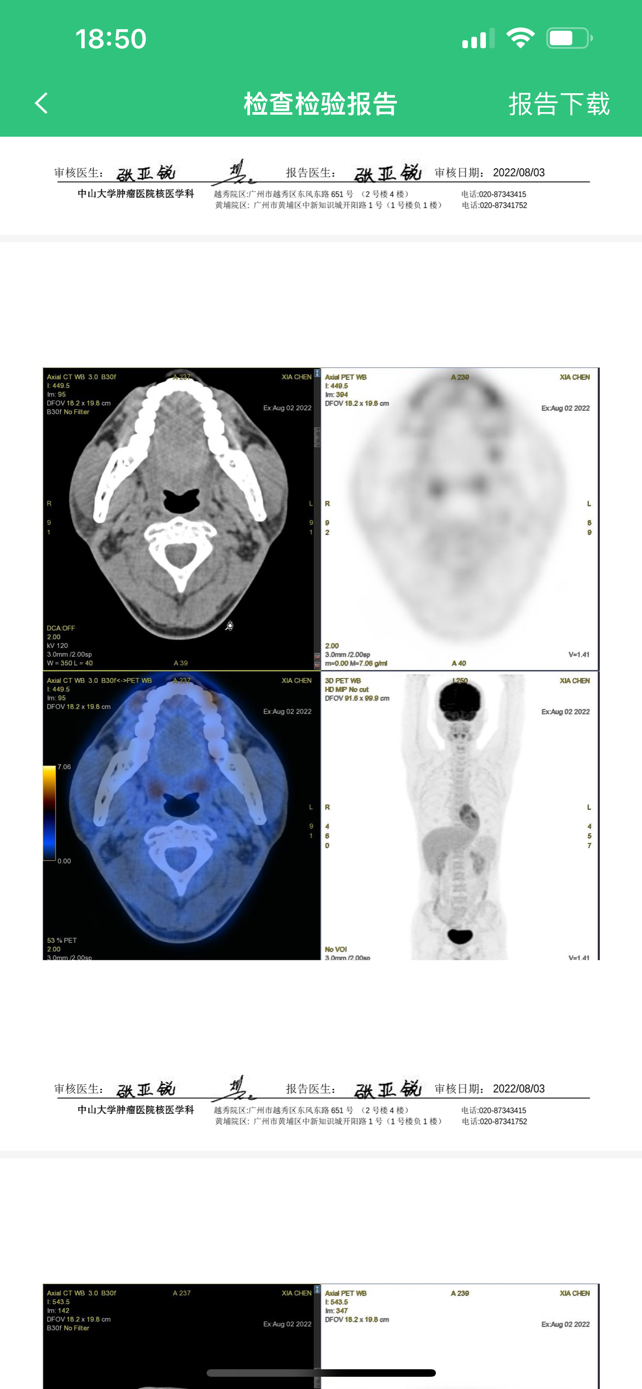

霍奇金淋巴瘤结节硬化型中期

霍结节硬化型

第五次化疗,医生告诉我还有七次,往后的每一次恢复期都变长一点,两个儿子最小的才两个多月,不知道自己能不能熬的住